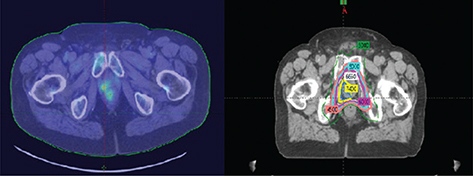

The advances in external beam radiation therapy treatment planning and delivery have positioned radiation therapy very well in the care of patients with prostate cancer. Image guidance secures and confirms the significant impact of intensity modulation on patient care. Because of the security of daily treatment execution, radiation oncologists have been able to adjust daily treatment dose to levels securing optimal outcome (3, 712). The process improvements in technology have permitted investigators to compress both daily and total treatment time without accelerated risk for normal tissue injury (3, 711, 13). Hypofractionation protocols decreasing the duration of treatment with increased daily dose are maturing and many investigators in the radiation oncology community consider compressed treatment programs moving towards the standard of care in patients with normal and near normal prostate anatomy and genitourinary function (811, 14, 15). Brachytherapy as monotherapy remains an outstanding therapy option for patients with low and early intermediate risk disease (3, 1619). Modern real time image guidance in the development and execution of the plan has made brachytherapy an outstanding treatment option. Brachytherapy with external therapy provides excellent outcomes in patients with less favorable intermediate-risk disease and high-risk disease when anatomically appropriate (Figure 2).

Fig 2

Figure 2. Permanent seed brachytherapy. This image shows the application of permanent seed brachytherapy in a high stage patient with the radiation dosimetry superimposed on the image courtesy of the Department of Radiation Oncology, UMass Chan Medical School and UMass Memorial Health.